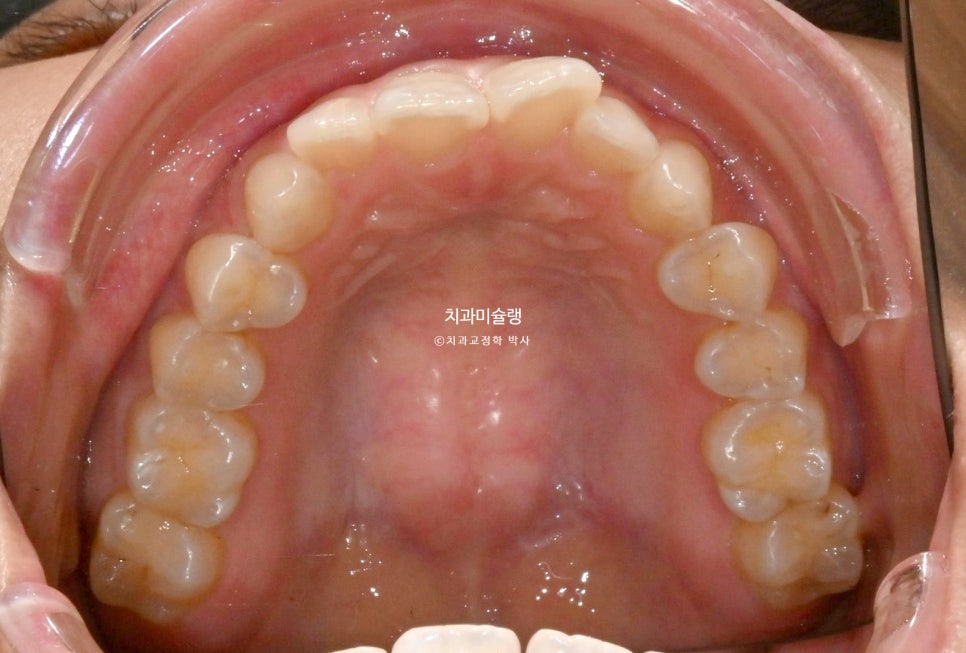

작년 여름, 교정치료를 위해 내원한 환자분 입니다.

앞니가 삐뚤하며 치축이 기울어져 있고 중심선이 약간 어긋나 있습니다.

그에비하면 어금니는 교합이나 배열이 좋은편입니다.

이 케이스는 앞니에 치아가 겹쳐진 부분이 펴지면서 블랙트라이앵글 발생이 예상됩니다.

아이테로 구강스캐너로 스캔을 한후 배열후 모습을 확인할 수 있는데, 이 과정에서 보이는 블랙트라이앵글의 대략적인 사이즈와 부위를 미리 시각화해서 볼 수 있죠.